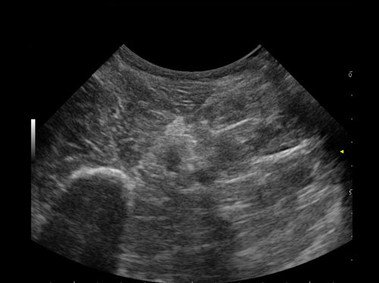

Das MyLab™One steht für das revolutionäre „Arm-held“ Hochleistungs-Ultraschallsystem mit 12”-Full-Touchscreen. Aufgrund seines geringen Gewichts und der Tragbarkeit kann es auch ohne Arbeitsfläche verwendet werden. Eine einzelne Person kann dieses Gerät aufgrund seiner einzigartigen Funktionen allein und selbstständig bedienen.

Das Ultraschallsystem MyLab™One zeigt exemplarisch den modernen Bedarf an Diagnosekapazitäten in verschiedenen Anwendungsbereichen: Radiologie, Kardiologie, Phlebologie, Frauenheilkunde, Orthopädie, Regionalanästhesie, Sportmedizin, Interventionell, Rheumatologie, Erste Hilfe, Notfallmedizin, Vaskuläre Reihenuntersuchungen, Allgemeinpraxis.